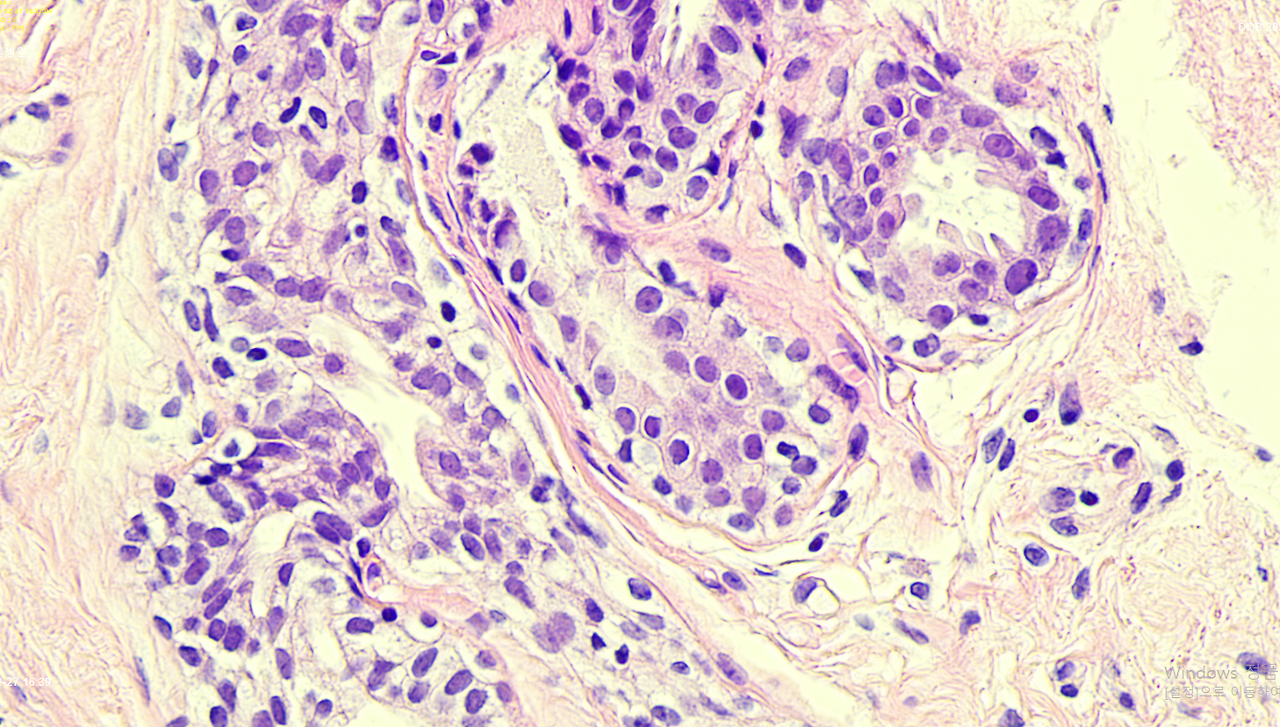

대학 병원에 제출 전에 동물 병원 현미경으로 조직 슬라이드를 보고 사진을 찍고, 우리 고양이 차트에 내 조직 사진을 저장해 두고 열심히 구글링과 챗GPT로 기준들을 체크했다.

증식된 내 유관세포들. 질서를 지키지 못하겠느냐..!

흐음.. 아무리 봐도 찜찜하다. 왜 이렇게 유관 내에 세포들이 빡빡하게 보이지... 기준이 2mm라고...?

대학 병원에서 조직 블럭을 더 슬라이드 쳐보면 확실해지려나.